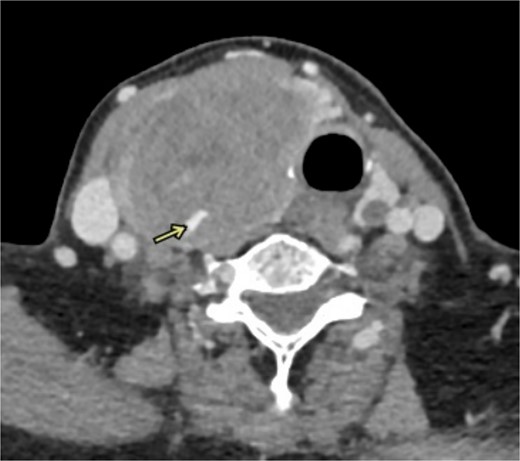

This case study describes a 76-year-old female with a history of type 2 diabetes and hypertension for fifteen years, controlled by her medication. She was swimming when she noted a sudden swelling in her neck. She presented to the emergency department of our hospital with right neck swelling for one-day duration. Physical examination shows a vitally stable patient with a localized neck mass not movable with swallowing and not associated with compressive symptoms. Computed tomography (CT) scan showed significant enlargement of the right thyroid lobe with heterogeneous predominantly hyperdense mass with mass effect on the airway with leftward deviation of the trachea (Fig. 1). Pre-operative CT Angiography showed active extravasation (Fig. 2). Also, there is a suspected right thyroid artery arching over the hematoma. The appearance of the artery raised the possibility of this artery being the cause of the hematoma. Then, a diagnostic angiogram was performed, which showed a dilated, ectatic-looking superior thyroid artery with flow into the hematoma, confirming the source of the hematoma. The patient successfully underwent angioembolization and hematoma evacuation without complications. During the procedure, an unexpectedly large solid component resembling thyroid tissue and a sac surrounding the hematoma were found. The patient was admitted to the Surgical Intensive Care Unit for post-operative monitoring and to prevent potential airway obstruction. The resected specimen was sent for further evaluation by pathology. Gross examination shows large dark brown hemorrhagic mass with thyroid tissue identified measuring 7.5 cm × 0.5 cm. Histopathology examination of the specimen revealed thyroid tissue with extensive hemorrhage and irregular dilated vascular spaces, as well as capillary-like vessels present in thyroid parenchymal tissue. Few thick-walled blood vessels were seen. These vascular channels are lined by bland endothelial cells (Fig. 3A, B). No cellular atypia, mitosis or solid growth pattern was observed. The vascular lining is diffusely positive for CD34, CD31, D2–40, and FLI1 (Fig. 3C, D). Given the above features of histopathology and immunohistochemistry studies, the diagnosis was compatible with primary thyroid hemangioma. Five months post-surgical resection, the patient’s follow-up indicates that she is in good health with no neck swelling, hoarseness of voice, or difficulty tolerating a regular diet. Her wound has healed without any signs of infection.

CT angiography shows active extravasations along the posterior aspect of the right thyroid lobe mass.